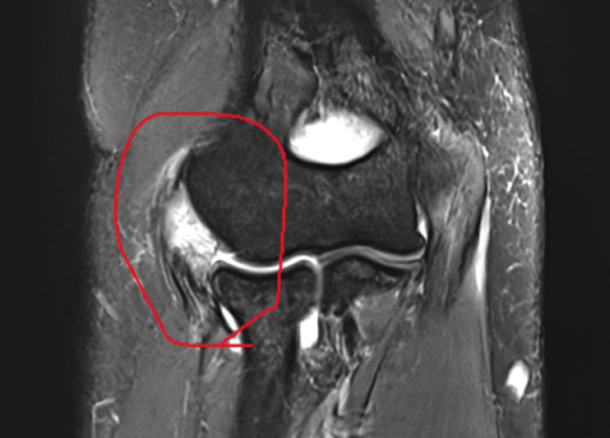

X-Ray, 초음파, MRI 등 검사

신경조직 압박, 신경증상 등 파악

진단 증상에 따라 치료계획을 세웁니다.

After 수술 후

1년 후 완전 정상화